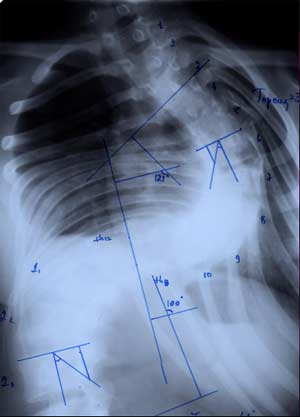

Нами проведен анализ 209 случаев

оперативного лечения сколиотической

деформации II - IV степени с использованием

двухпластинчатого эндокорректора с

многоуровневой фиксацией. Срок наблюдения

составил от 1 до 4-5 лет с наличием

корректора и от 1 до 3 лет после его

удаления. Средний возраст 13,8 года.

Врожденный сколиоз был только в 3,83%

случаев. Деформация с наименьшим углом

по Коббу составила 21°, с наибольшим

124°. Основное число прооперированных

больных было с углом искривления в

диапазоне 31°-70°. Среди них у 43% угол

искривления составил 51°- 60°.

У больных со II степенью деформации

коррекция составила 96,56 - 100%

|

При

сколиозе III степени - 88,19 - 91,26%.

сколиозе IV степени с углом деформации

в диапазоне от 51° до 70° коррекция

составила от 79,2 до 84,8%. С углом от 71° дог

80° - 73,3 - 86,5%. С искривлением от 81° до 122°

удалось достигнуть одномоментно

коррекции в пределах 72,7 - 73,8%.

Коррекция

ротационной деформации при II степени

сколиоза была 61,83%.

При III степени удалось добиться В среднем

коррекции на 59,2%, а при IV степени только

на 34,04%. Более низкий процент коррекции

сколиотической деформации, как боковой,

так и ротационной, объясняется тем, что

как правило оперативному лечению с IV

степенью подвергаются пациенты с

запущенными стадиями заболевания, как

правило с законченным ростом, более

взрослые, с достаточно уже жестким

фиксированным позвоночником. И не менее

важно то, что угол деформации большой,

часто более 80° - 90°, а это при одномоментной

коррекции чревато неврологическими

осложнениями различной степени тяжести.

Для

достижения более полного эффекта

коррекции в момент операции при тяжелых

степенях сколиоза с выраженной реберной

деформацией мы дополнительно прибегаем

к торакопластике на вершине искривления.

При этом производится остеотомия ребер

с частичной их резекцией. Т.е. совмещаем

две операции: коррекция сколиотической

деформации и торакопластика реберного

горба. Кроме этого эффективность

коррекции при тяжелых степенях повышает

и увеличение жесткости пластин, что

достигается использованием не двух

пластинчатых корректоров, а трех- и

четырех пластинчатых. Причем, комбинация

установки пластин может меняться в

зависимости от необходимости у конкретного

ребенка. Планирование оперативного

вмешательства и подбор корректора

проводится строго индивидуально для

каждого больного.